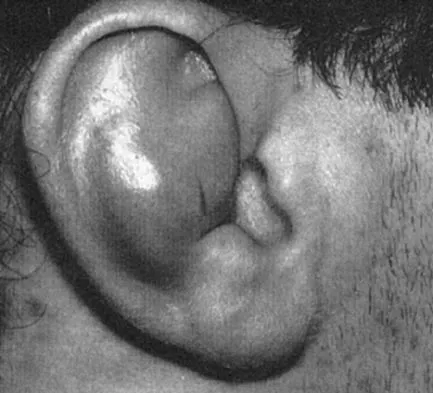

Figure 3 shows the clinical photograph of a wrestler who has an acute mass in his ear. He does not wear protective headgear. The area is mildly tender and without erythema. Management should consist of